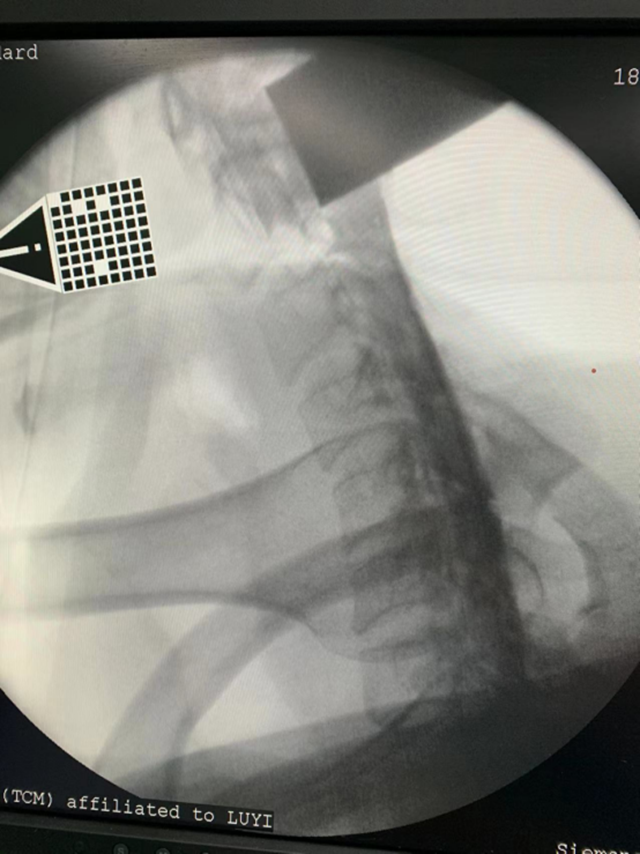

通过颈椎磁共振检查,显示游先生颈5/6和颈6/7椎间盘均有突出,尤其是颈6/7椎间盘向右侧突出明显,压迫了脊神经根造成了右侧肢体酸痛、麻木,诊断为颈椎病,需要手术治疗。

据张英教授介绍,颈椎间盘突出胶原酶融盘术只需要对患者进行局麻,在影像学精准定位下,耗时约30分钟,将导管固定在突出组织部位,再注射经过精准定量的药物胶原酶,对突出组织进行化学溶解,对正常组织不影响。该手术创口很微小,只有1个针眼,术中几乎没有出血,术后恢复时间缩短为5-7天,医疗费用减少一半。